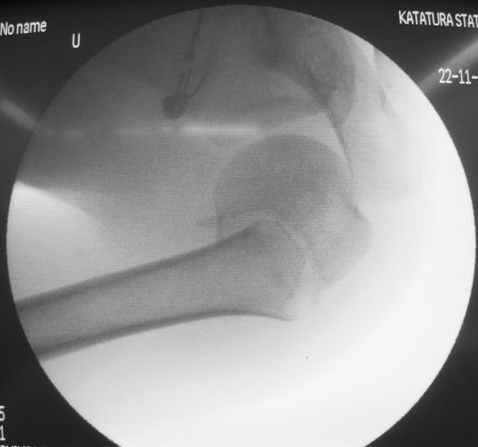

Здесь случай перелома-вывиха плеча, больному 56 лет, после "дважды" закрытой неудачной репозиции, опять же ургентно взяли в операционную, после полного общего обезболивания попытались сделать репозицию, и фиксацию провели спицами.

Больной находился в повязке, примерно напоминяющей косыночную, рекомендованы движения в локтевом суставе и маятниковые движения в плече, спицы удалены в три недели (были случаи миграции)

Больной амбулаторный, предупрежден на случай осложнения АВН головки.